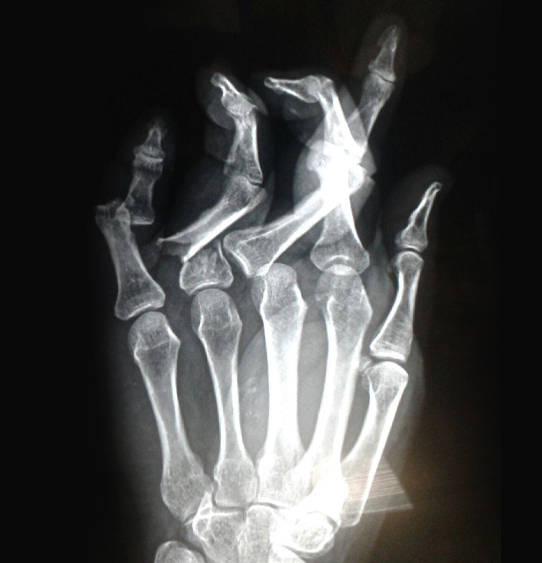

Hand Surgery

The hand and wrist are very complex; therefore, seeing a hand specialist can yield the best solution for conditions of the hand, wrist and arm. The Joyner Hand provides a number of surgical and non-surgical procedures for a variety of hand and arm conditions.